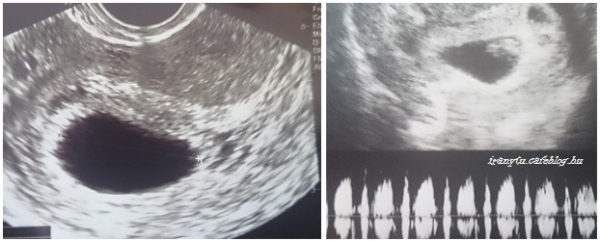

Izgalmak nélkül nem úsztuk meg a 7. hetet sem, úgy tűnik a káoszos időszak csitulása még várat magára…